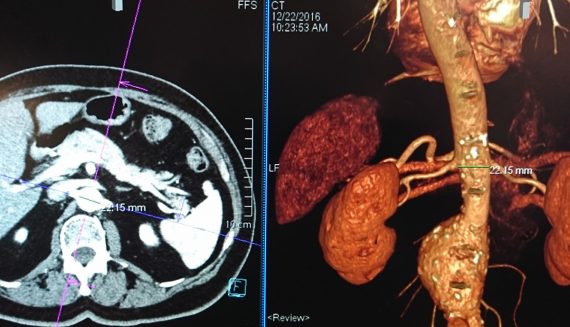

En sık bacak toplardamarlarında görülen bu hastalığın sıklığı 1000de 1-2dir. Genellikle 40-50 yaş ve sonrasında görülen bu hastalık seyrek olmakla …Devamı